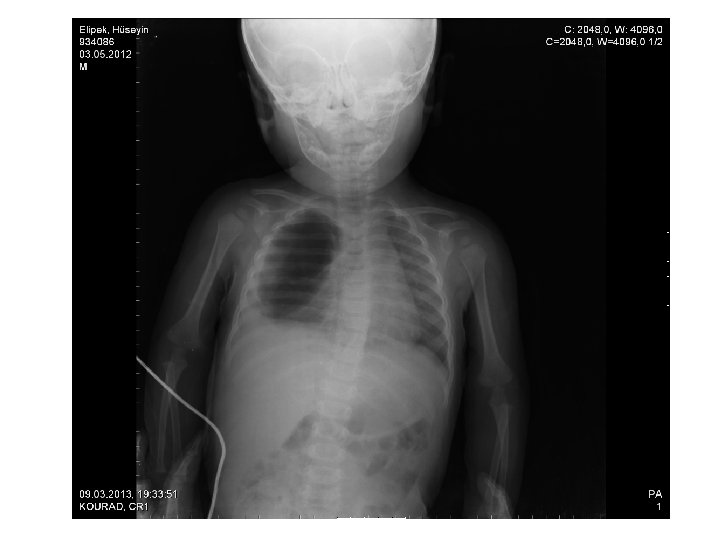

2 hafta önce ateş, kusma, ishal şikayetiyle başvurduğu hastanede yatırılarak tedavisi başlanan hastanın yatışının 5. gününde ani solunum sıkıntısının başlaması ve morarmasının olması üzerine hastanın akciğer grafisi çekilmiş.

ÖZET • 10 aylık, erkek hasta, ateş kusma ve ishal şikayetleri ile izlenirken solunum sıkıntısı gelişiyor. • Takipne, saturasyon düşüklüğü, • Sağ akciğerde yaygın ral, sağ üst zonda solunum seslerinde azalma, • PA AC grafisnde sağ akciğerde havalanma artışı • AFR artışı mevcut • ÖN TANI?

Toraks Tomografi(12/03/2013) • Sağ akciğer alt lobda içerisinde hava sıvı seviyesi izlenen kalın duvarlı ve duvar kontrastlanması gösteren abse ile uyumlu lezyon. • Sağ akciğer üst lob posterior ve alt lob superiorda pnömonik konsolidasyon. • Sağda plevral effüzyon.